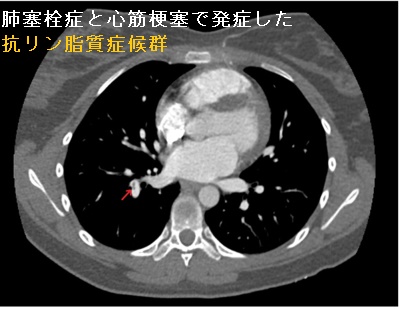

肺血栓塞栓症(肺梗塞)はエコノミー症候群(エコノミークラス症候群)として有名ですが、抗リン脂質抗体症候群でもおこります[Open Access Maced J Med Sci. 2015 Dec 15;3(4):705-9.]。

- 胸部造影CTでほぼ確定